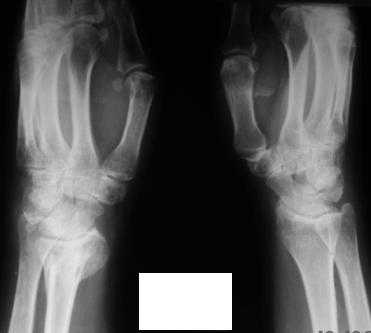

Обратилась женщина, 55 лет. Травма 3 месяца назад, лечилась по месту жительства (Рис.1). Косорукость, боли, ограничение движений. Досняли - рис.2-6. Хотелось-бы услышать мнения  об объеме операции.